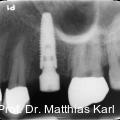

Parallel zur Entwicklung verkürzter Behandlungskonzepte haben sich auch die Außengeometrien zahnärztlicher Implantate hin zu aggressiveren Gewindeformen und konischen Grundkörpern entwickelt. Fotos: © Prof. Dr. Matthias Karl